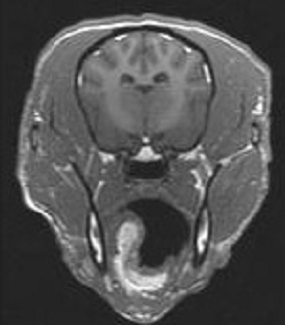

Dog brain segmented into grey matter, white matter and cerebrospinal fluid Transpharmation has experience in image processing of all modalities. Image processing extracts quantitative data from images. This can range from basic morphometric measurements made from images such as bone length or hippocampal volume to complex segmentation based on image signal intensities.